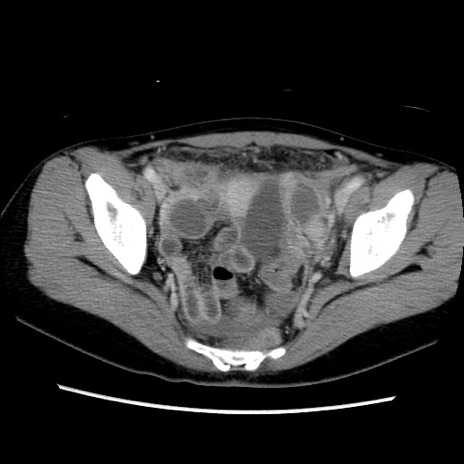

症例39(横断像)

【症例】40歳代女性

【主訴】上下腹部痛

【現病歴】2日目から下腹部痛あり。夜間は痛みで眠れなかった。昨日より上腹部痛と下痢が出現。臥位で痛みは軽快したため、休んでいた。本日になって臥位でも立位でも痛みが強くなってきたため救急要請。

【既往歴】子宮内膜症

【身体所見】部:平坦・軟、左上下腹部に圧痛あり、反跳痛あり。

【データ】WBC 21800、CRP 26.78